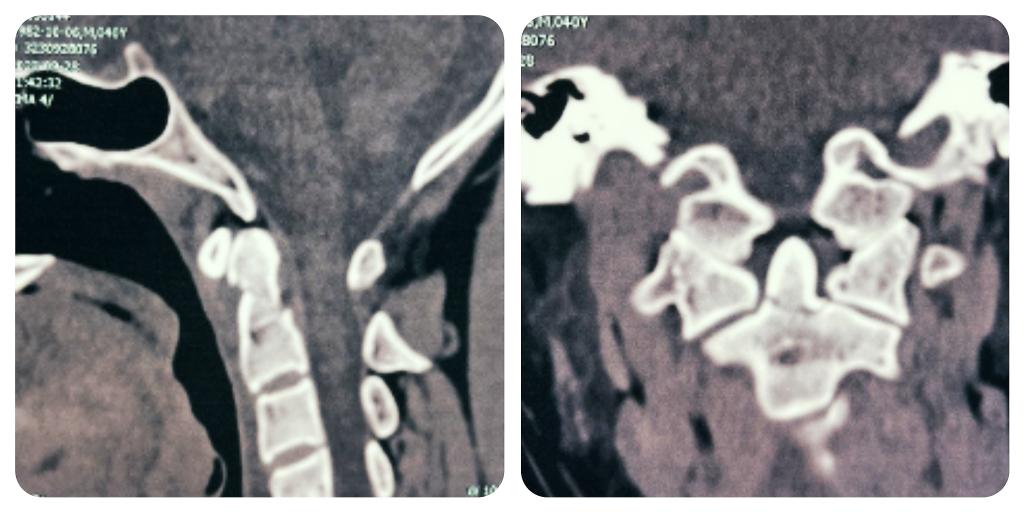

术前颈椎CT

以往此类骨折,患者均需转院省城医院。入院后,肖强教授带领我院骨科脊柱团队详细检查病人及审阅患者影像资料,认为患者齿状突骨折Ⅱ型,寰枢椎不稳,手术指征明确,为方便患者的就医,肖强教授决定利用国庆假期,在我院为患者行手术治疗。经过充分术前准备,制定了周密手术计划,于9月30日成功完成了颈后路寰枢椎椎弓根螺钉内固定术,术中透视,齿突骨折解剖复位,寰枢椎椎弓根螺钉位置良好,手术顺利,出血约50毫升,历时约1小时,术后患者状态恢复良好,现佩戴颈托已下地活动。